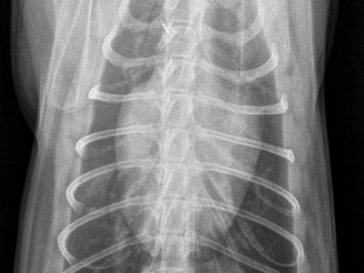

Thorax Röntgen

«Valentins-Herz»: Ventro-dorsale Aufnahme mit vergrösserter Herz- Silhouette